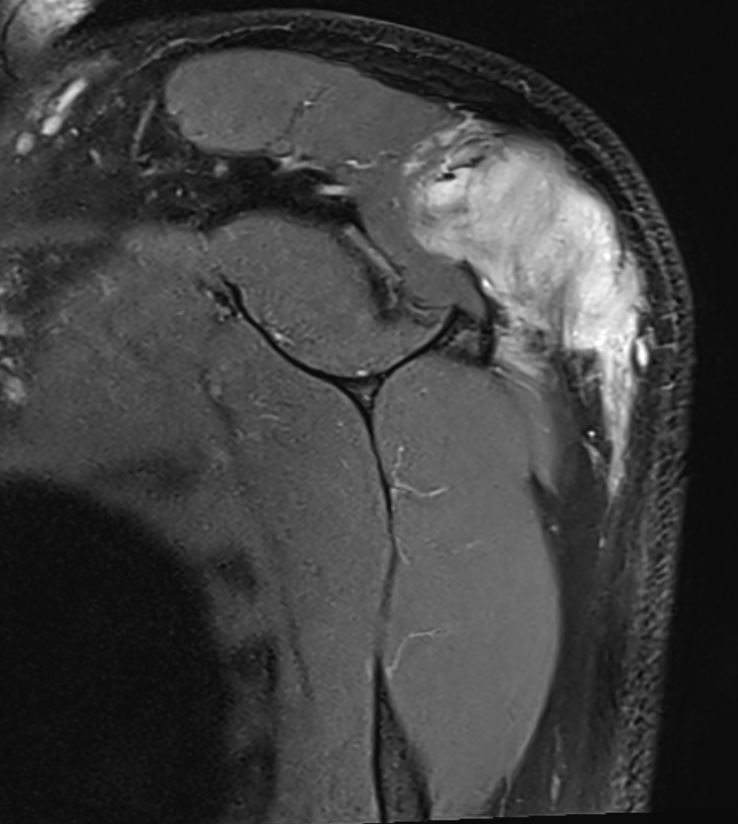

MRI

Soft tissue mass